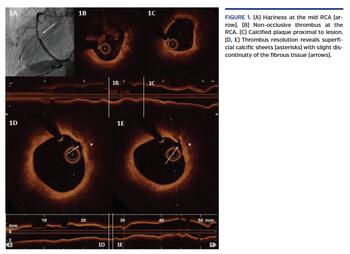

We present the case of a 63-year-old woman, former smoker, transferred to the catheterization laboratory for primary percutaneous coronary intervention in the midst of anterior ST-segment elevation myocardial infarction. Coronary angiography showed acute total occlusion of the proximal left anterior descending (LAD) (Video 1). After the guidewire passed through the distal LAD, TIMI-3 flow revealed severe proximal stenosis, which was treated with an everolimus-eluting stent with good outcome (Video 2). Afterward, angiographic haziness was recognized at the mid right coronary artery (RCA) (Figure 1A). Optical coherence tomography (OCT) exhibited non-occlusive thrombus (Figure 1B) and calcified plaques were observed proximal to the lesion (Figure 1C). Tirofiban perfusion was administered. After 10 days under dual-antiplatelet therapy (DAPT) with aspirin and prasugrel, OCT was repeated, displaying thrombus resolution with superficial calcific sheets (SCS) (Figures 1D and 1E) and minimal disruption of overlying fibrous tissue (Figure 1D-E: arrows) without compromise of the luminal area. Prolonged DAPT was recommended.

SCS has been implicated recently in the pathogenesis of acute coronary syndromes, and could have caused the acute RCA thrombosis in our patient. The underlying mechanism seems to be different from eruptive calcified nodules, and different theories have been speculated. OCT was useful to characterize in vivo SCS and exclude other causes of acute coronary syndromes, such as plaque erosion. Nevertheless, the management and potential prognostic and clinical implications of this type of calcified plaque are not clear, so further investigation needs to be done.